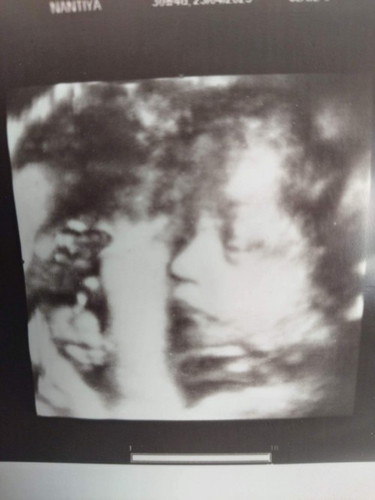

ลูกสาวตัวน้อยจมูกโด่งตาโต สมใจพ่อกับแม่จริงๆเรย

อันนี้ซาวตอนกี่วีคคะ ชัดมากก ของเราซาวตอน30วีค ยังไม่ชัดขนาดนี้เลยค่ะ

จมูกน้อนนหืออ ของบ้านนี้32week ยังไม่เคยให้แม่เห็นหน้าเลย ปิดตลอด

ชัดมากจมูก ซาวตอนกี่วิคค่ะ

ซาวตอน30วิคจร้า

จมูกน้อง พุ่งมากกกกกก

ซาว3มิติจร้า

จมูกน้องพุ่งมาก